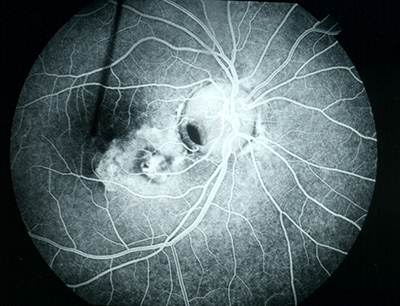

Central retinal vein occlusion of the right eye.

Central retinal vein occlusion (CRVO) blocks the main vein in the retina, the light-sensitive nerve layer at the back of the eye. The blockage causes the walls of the vein to leak blood and excess fluid into the retina. When this fluid collects in the macula-the area of the retina responsible for central vision-vision becomes blurry.

Floaters in your vision are another symptom of CRVO. When retinal blood vessels are not working properly, the retina grows new fragile vessels that leak blood into the vitreous, the fluid that fills the center of the eye. Blood in the vitreous clumps and is seen as tiny dark spots, or floaters, in the field of vision.

In severe cases of CRVO, the blocked vein causes painful pressure in the eye. Retinal vein occlusions commonly occur with glaucoma, diabetes, age-related vascular disease, high blood pressure, and blood disorders.